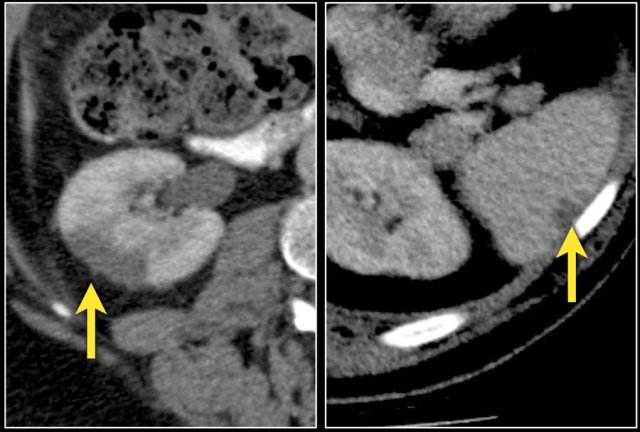

Bleeding in Angiomyopiloma

Due to the abnormal vessels within an AML, it is prone to bleeding.

Patients can present with acute flank pain due to spontaneous hemorrhage.

The risk of hemorrhage increases with size.

Embolization was performed to stop the bleeding.

Preventive embolization is recommended in tumors larger than 4 cm, even in asymptomatic patients.

Notice the large vessels in the AML in the left kidney.